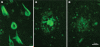

Methods: AD cases with a Braak neurofibrillary tangle stage of more than IV were identified from a brain bank database. By use of thioflavin-S fluorescence microscopy, we assessed the density and the distribution of neurofibrillary tangles in three cortical regions and two hippocampal sectors. These data were used to construct an algorithm to classify AD cases into typical, hippocampal sparing, or limbic predominant. Classified cases were then compared for clinical, demographic, pathological, and genetic characteristics. An independent cohort of AD cases was assessed to validate findings from the initial cohort.

Findings: 889 cases of AD, 398 men and 491 women with age at death of 37-103 years, were classified with the algorithm as hippocampal sparing (97 cases [11%]), typical (665 [75%]), or limbic predominant (127 [14%]). By comparison with typical AD, neurofibrillary tangle counts per 0.125 mm(2) in hippocampal sparing cases were higher in cortical areas (median 13, IQR 11-16) and lower in the hippocampus (7.5, 5.2-9.5), whereas counts in limbic-predominant cases were lower in cortical areas (4.3, 3.0-5.7) and higher in the hippocampus (27, 22-35). Hippocampal sparing cases had less hippocampal atrophy than did typical and limbic-predominant cases. Patients with hippocampal sparing AD were younger at death (mean 72 years [SD 10]) and a higher proportion of them were men (61 [63%]), whereas those with limbic-predominant AD were older (mean 86 years [SD 6]) and a higher proportion of them were women (87 [69%]). Microtubule-associated protein tau (MAPT) H1H1 genotype was more common in limbic-predominant AD (54 [70%]) than in hippocampal sparing AD (24 [46%]; p=0.011), but did not differ significantly between limbic-predominant and typical AD (204 [59%]; p=0.11). Apolipoprotein E (APOE) ɛ4 allele status differed between AD subtypes only when data were stratified by age at onset. Clinical presentation, age at onset, disease duration, and rate of cognitive decline differed between the AD subtypes. These findings were confirmed in a validation cohort of 113 patients with AD.